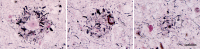

Figure 1

'Classical' Aβ (senile) plaques in the cortex of persons who had died with Alzheimer's disease (AD). Left, a plaque stained with the Naoumenko-Feigin silver method and periodic acid-Schiff (PAS) counterstain; an amyloid core (dark pink) is surrounded by profuse abnormal neurites (black). Right, a plaque immunostained with antibody 4G8 to the Aβ protein (brown) along with a Nissl counterstain (blue); glial nuclei are visible in the region between the plaque core and outer corona, and within and surrounding the corona. Bar = 20μm for both panels.